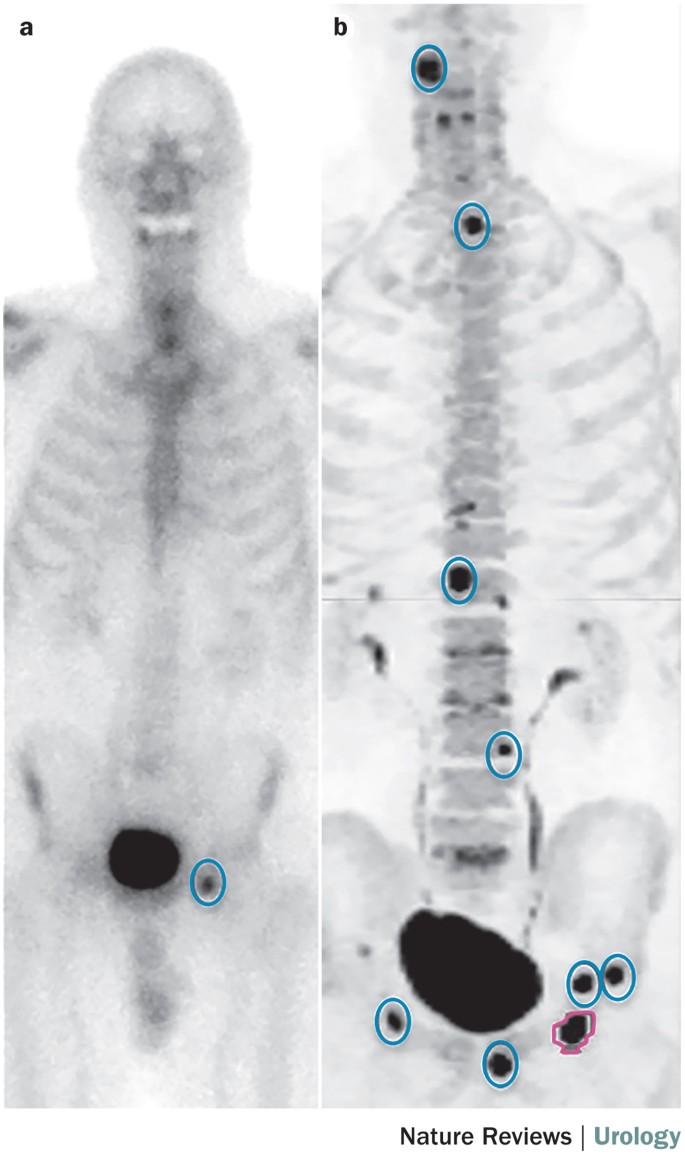

Imaging and evaluation of patients with high-risk prostate cancer | Nature Reviews Urology

image size: 685x1155